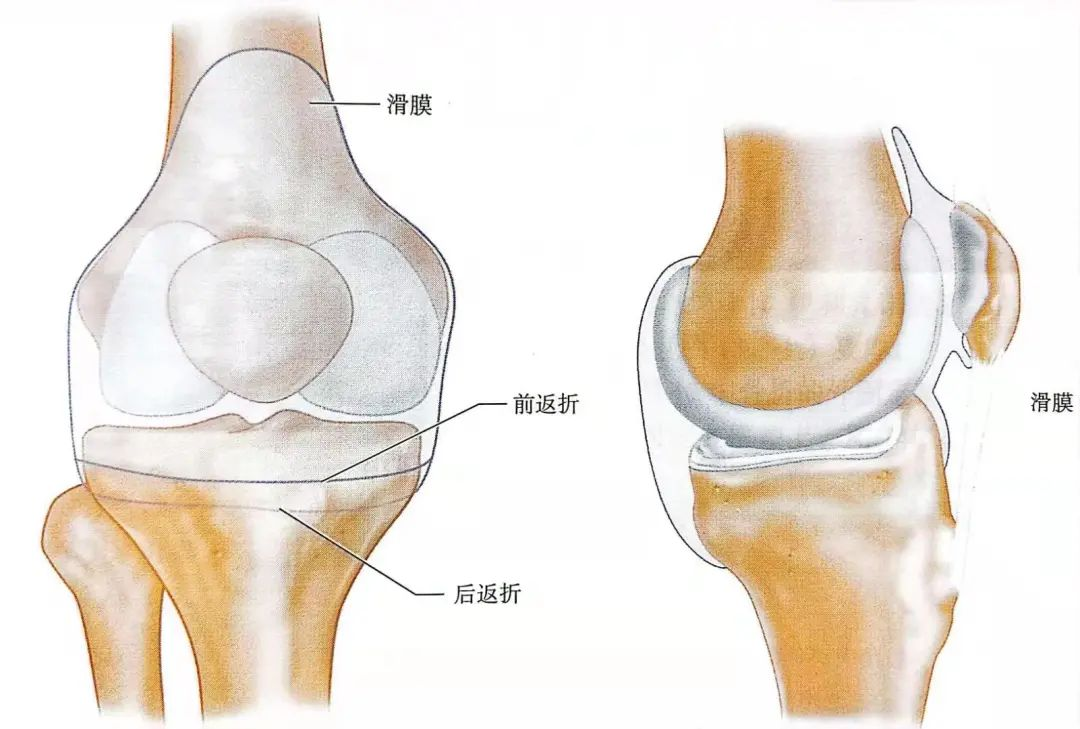

为了减少感染的风险,克氏针和钢针需要避开关节囊。因此,克氏针和钢针固定位置离胫骨平台上缘要大于1cm。

▲示意图